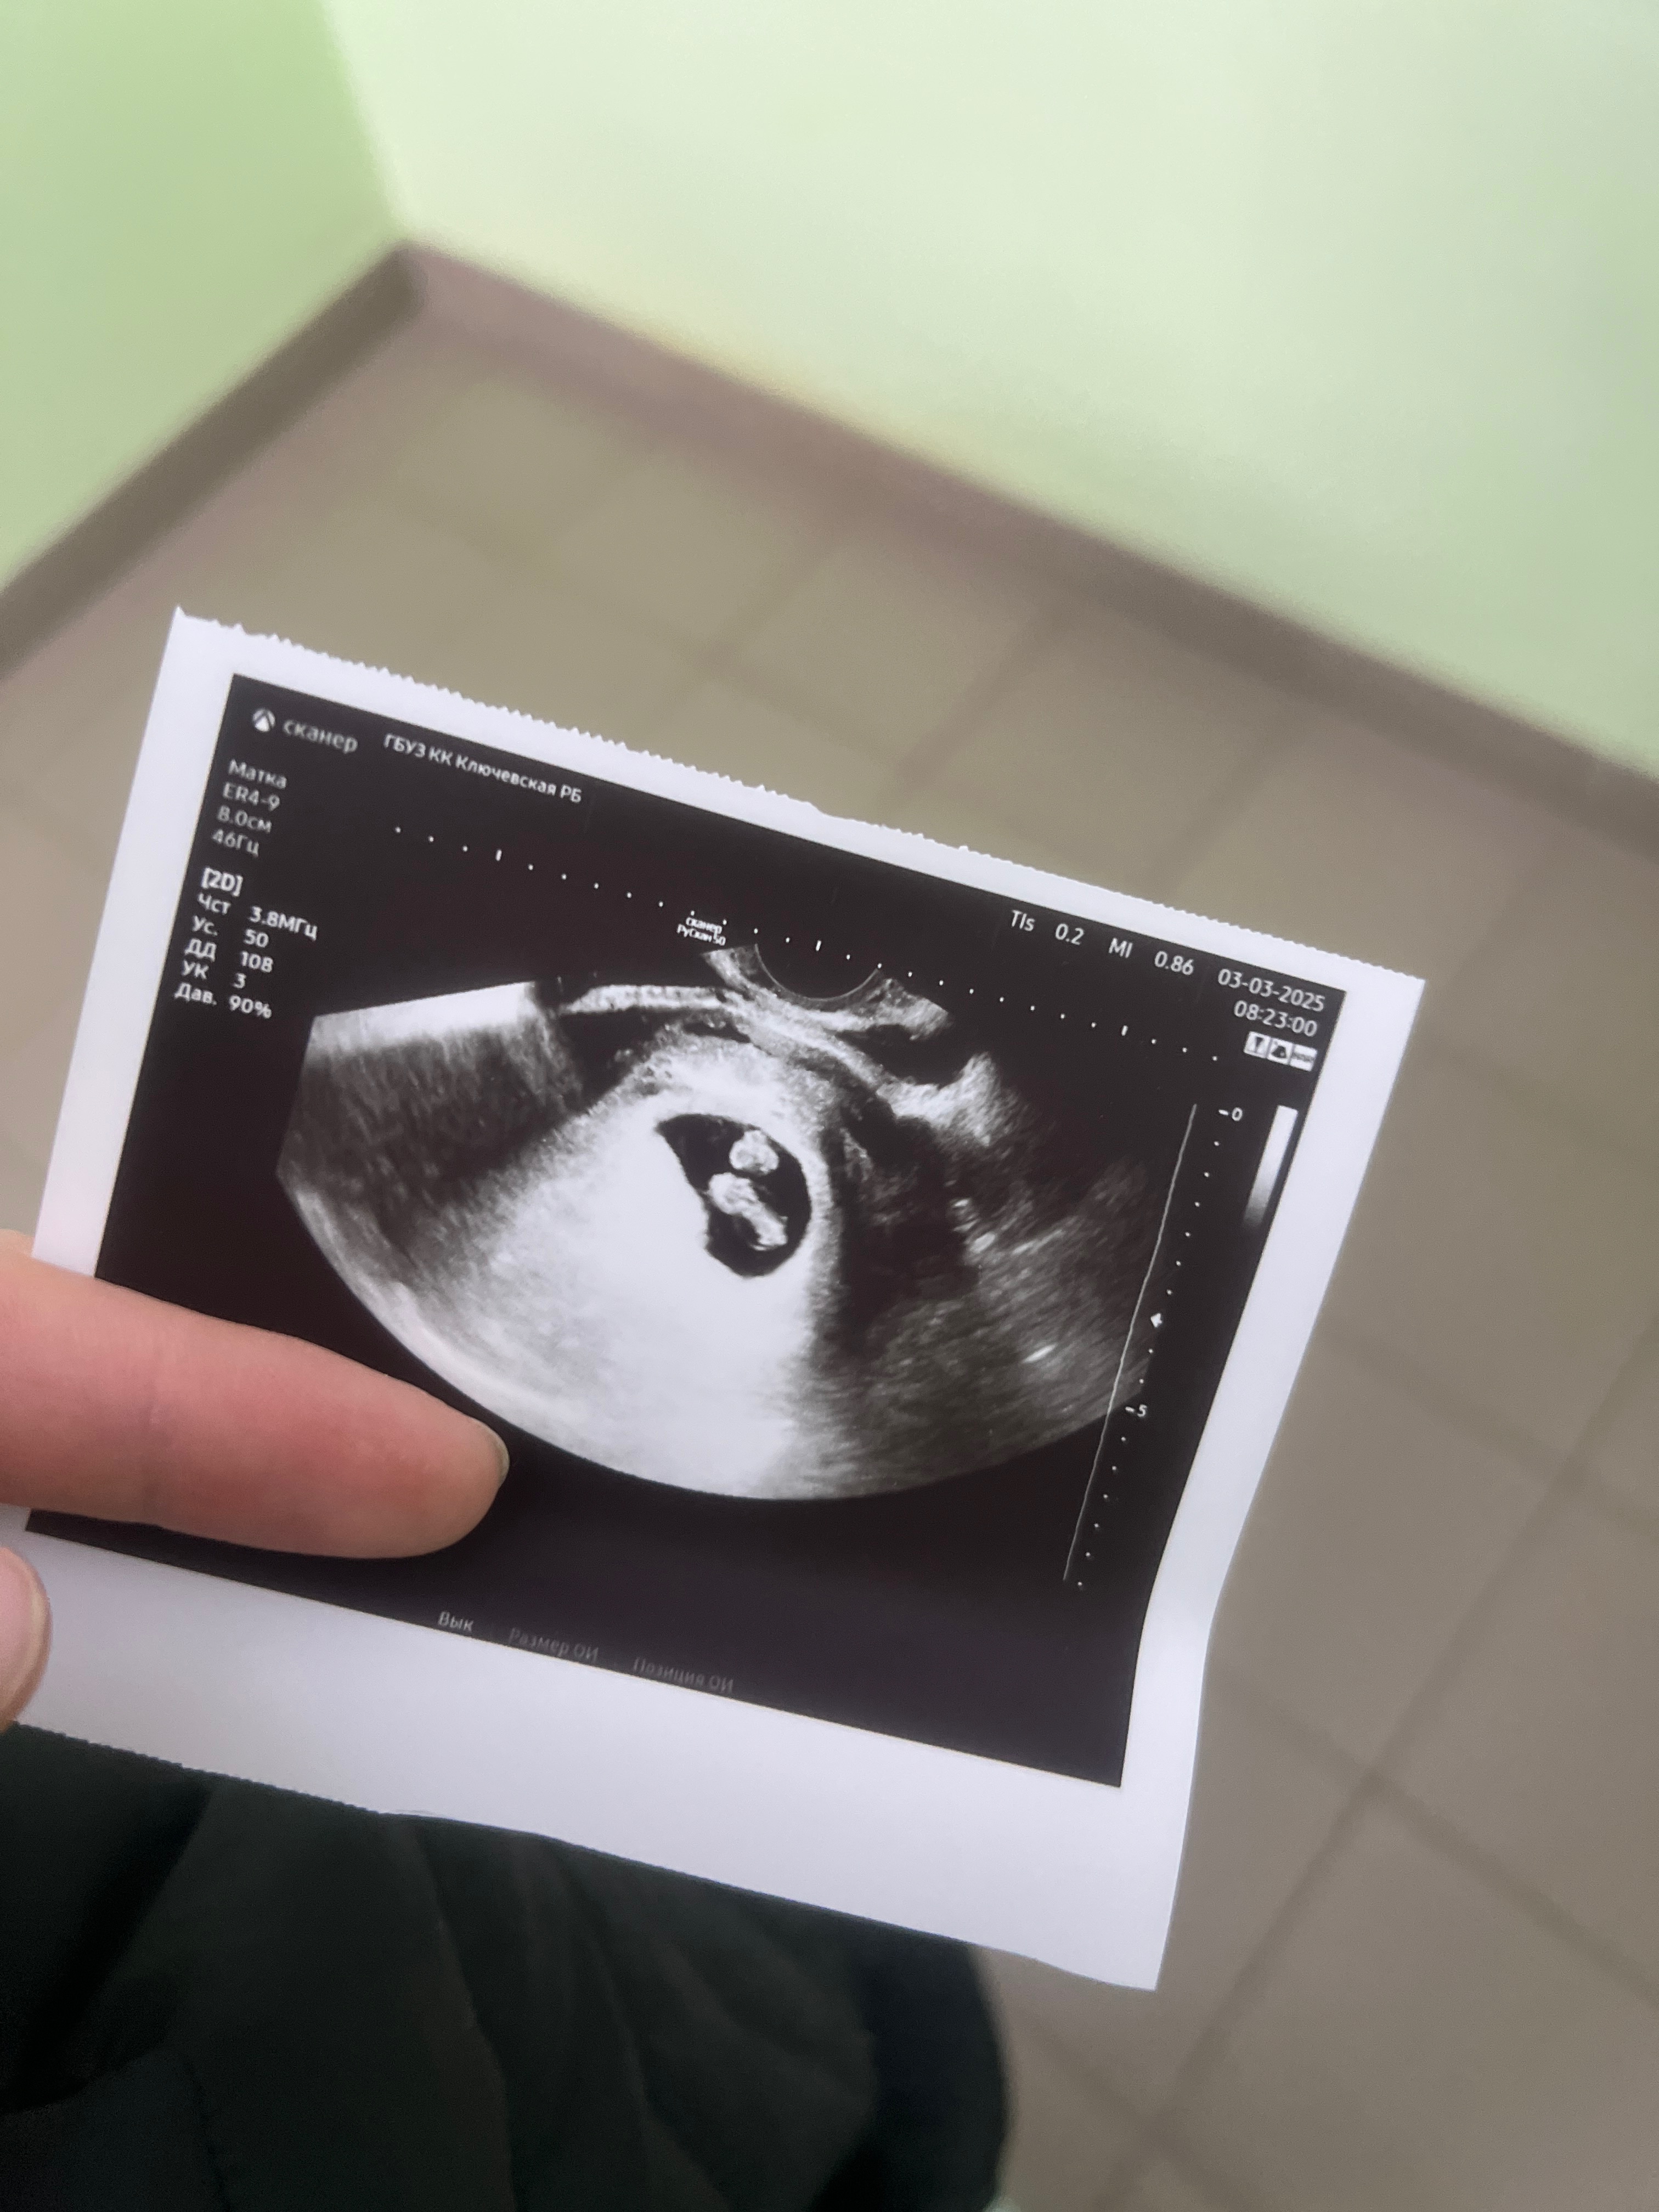

Изображение Вот моя однояйцевая двойня. Это значит, что оплодотворенная яйцеклетка поделилась. Не важно были в роду двойняшки или нет) у меня и у супруга никого нет ни близнецов ни двойняшек

An, я та курица, которая смотрит на снимок узи 😁 видит эмбрион и не понимает, а где второй, это сбоку или два снимка разных эмбрионов. Подскажите пожалуйста 🙏 на каком сроке снимок этот делали ?

Анаставитушка, на первой фотке один малыш, на второй фотке второй малыш Сфоткать их вместе сложно До 7-8 недели не видели второго малыша На 8.5 увидели двоих

An, у меня в 6 недель вообще никого не было, только пустое плодное яйцо и желточный мешок, а вот уже к 8 неделе двоих она нашла. Поэтому я в ступоре сидела, не сразу осознала. Спасибо за отзыв 🙏

А в чем сомнения? В компетенции специалиста? Она же сказала два сердцебиения. На одном фото УЗИ никогда не будет 2 эмбриона как на картинке. ТК они все время перемещаются. Потому сначала один будет хорошо виден, потом второй если поднадавить и под другим углом датчик поставить. Тут важнее в заклчении моноамниотическая или диамниотическая двойня.

Ну и размеры важны , конечно. Важно чтобы не сильная разница в размерах была. (На фото УЗИ, повторюсь не смотрите, там ракурсы разные)

Ольга, сомнения возникли потому что она сначала сомневалась, с фразой «а не многоплодная ли у тебя беременность?» Потом уже экран повернула: «вот видишь и второе сердцебиение пульсирует», смутило, что один эмбрион чуть меньше, второй по больше. Я просто в этот момент уже головой выпала с реальности и дальше честно ничего не помню( потому что успокоилась, что бьется сердце и услышала. Вообще вылетело с головы за описание взять, она унесла его в книжку вклеила и я на автопилоте с снимком в руках пошла домой. А смотрю на снимок, ну вроде тут двое, а может мне кажется. И все ступор какой то. К сожалению справить мнения специалистов не могу, нахожусь в конкретной жжжжж России и сходить больше даже платно некуда, смогу только в первых числах марта и вот сижу не понимая.

Анаставитушка, а чего тогда сомневаться и удивляться? Или сомневаетесь в компетенции врача? На фото две горошины)

А что вас смущает? 2 бусики же на фото))) мои поздравления.

Наталья, просто одну бусинку прям видно, а вторая не могу понять, то ли боком то ли почему размер такой

Ждем вашего скрининга) я верно поняла из комментариев, что 13 марта он у вас? Вы потом отпишитесь) на узи видно две креветочки)

Ну вы даёте, какие сомнения😂 Две креветки

И почему у вас сомнения? 2 😍